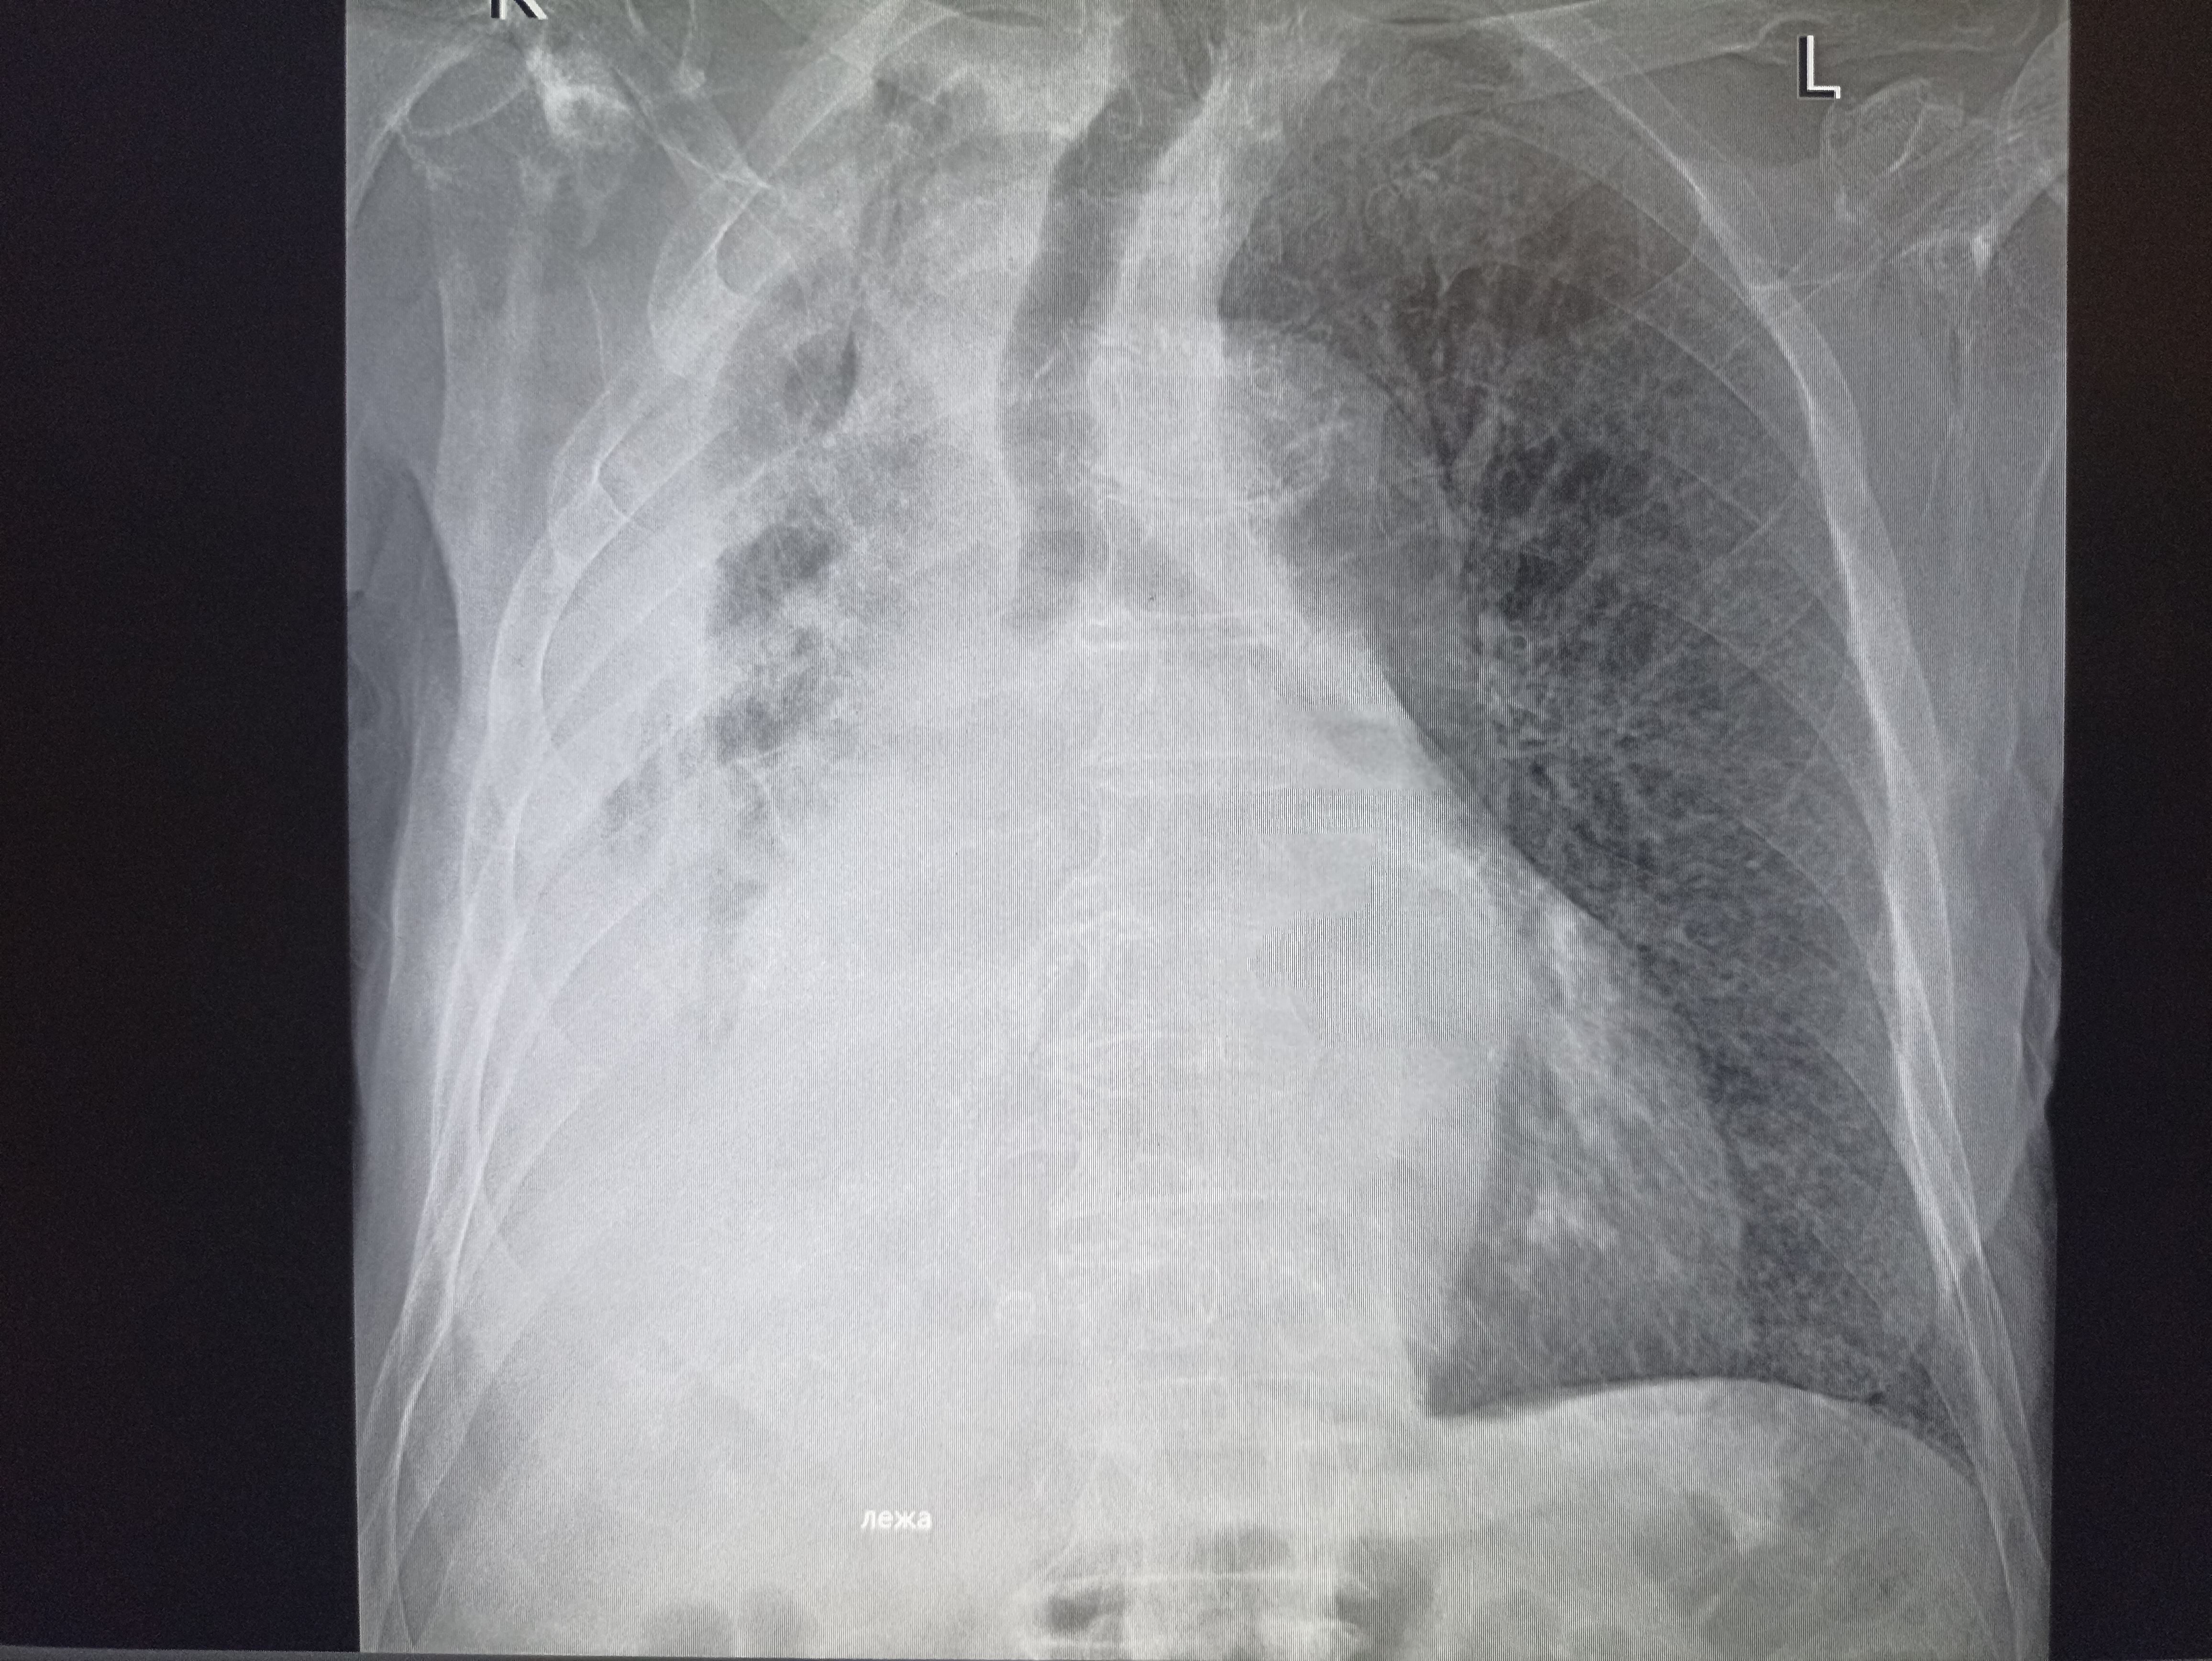

И снова здравствуйте! Сегодня! В этом тредике! Мы будем с вами общатся и играть в доктора! Я буду вам постировать фоточки, а вы угадывать пиздецомы! Я все еще нихуя не успеваю, пытаюсь описать за 25 число, сегодня задержусь наверное после работы опять пытаясь нагнать нагрузку :-(